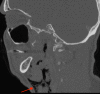

Pneumoparotid refers to the presence of air within the parotid gland and pneumoparotitis indicates overlying inflammation or infection. Several physiologic mechanisms exist to prevent the reflux of air and oral contents into the parotid gland, however, these safeguards can be overcome by high intraoral pressures, thus provoking pneumoparotid. Whereas the relationship between pneumomediastinum and air dissecting up into cervical tissues is well understood, the relationship between pneumoparotitis and free air traveling downwards through contiguous structures within the mediastinum is less defined. We present a case of a gentleman who experienced the sudden onset of facial swelling and crepitus in the context of inflating an air mattress with his mouth, who was ultimately found to have pneumoparotid with consequent pneumomediastinum. Discussion of this unusual presentation is important to facilitate recognition and treatment of this uncommon pathology.